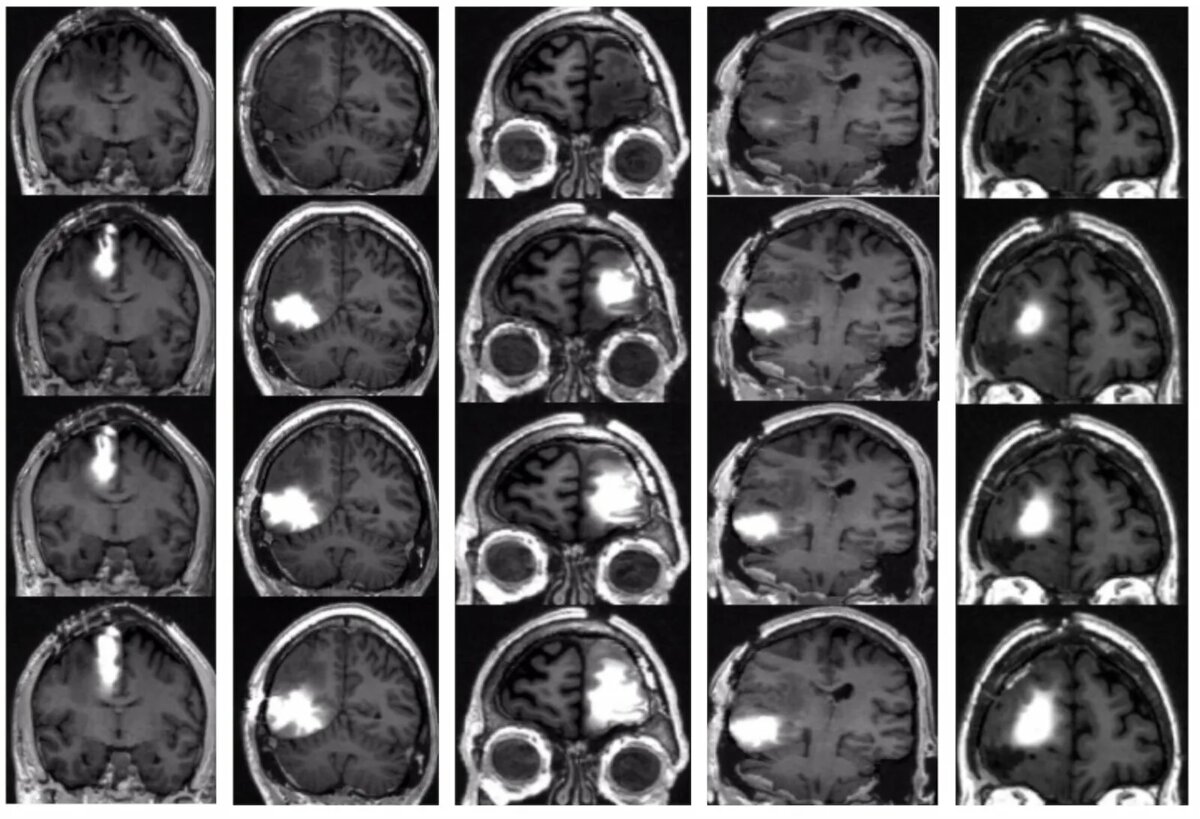

Рак мозга — это не одно заболевание, а целая группа опухолей, которые могут быть первичными (начинаются в самом мозге) или вторичными (метастазы из других органов — например, лёгких, груди, кожи). Вторичные встречаются чаще, но когда говорят «рак мозга», обычно имеют в виду именно первичные опухоли.

Самые известные из них — глиомы (включая агрессивную глиобластому), менингиомы (чаще доброкачественные), аденомы гипофиза и другие. Некоторые растут медленно годами, другие — стремительно, за недели.